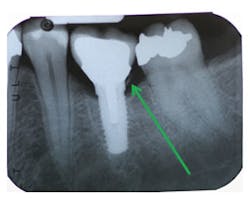

According to Present and Levine, many implant clinicians, for esthetic reasons, like to place margins of their implant restorations greater than 2 mm subgingivally.8 They emphasize that researchers have demonstrated that it is almost impossible to remove excess cement around implant restorations with subgingival margins greater than 1.5 mm.8 Radiographic examination doesn't always reveal remnants of cement, particularly on buccal/lingual surfaces.8 Levine reports that peri-mucositis can be observed from as early as six weeks to over nine years.

11. Dental radiographs are not a reliable method for excess cement evaluation.11